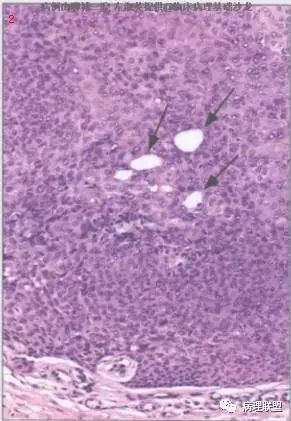

@左淑英 左老师,病例1,应该是汗腺来源,,考虑为汗孔瘤,细胞形成突起突入真皮,与表皮相连,第二张图箭头指向表示导管分化的结构,第三张图显示其纤维血管性间质,第四张图显示其有色素沉着,不知道对不对,今天我也遇着一个皮肤病例,您也给看看@左淑英

单纯性汗腺棘皮瘤可能好一些

师父说的对,这个仅仅在表皮内,@刘香丽 @赖娇 看看程老师病例,跟我发的比较一下

@赖娇 不一样的,一个局限在表皮内看那张切片图就可以看到,细胞都是一样的,如我师父说的 ,比喻的简单明了,细胞都是那种空空的样子,汗腺棘皮瘤是汗孔瘤的一个亚型,有人这样认为,

@左淑英 左老师,汗1考虑单纯汗腺棘皮瘤;汗2考虑色素性汗孔瘤。